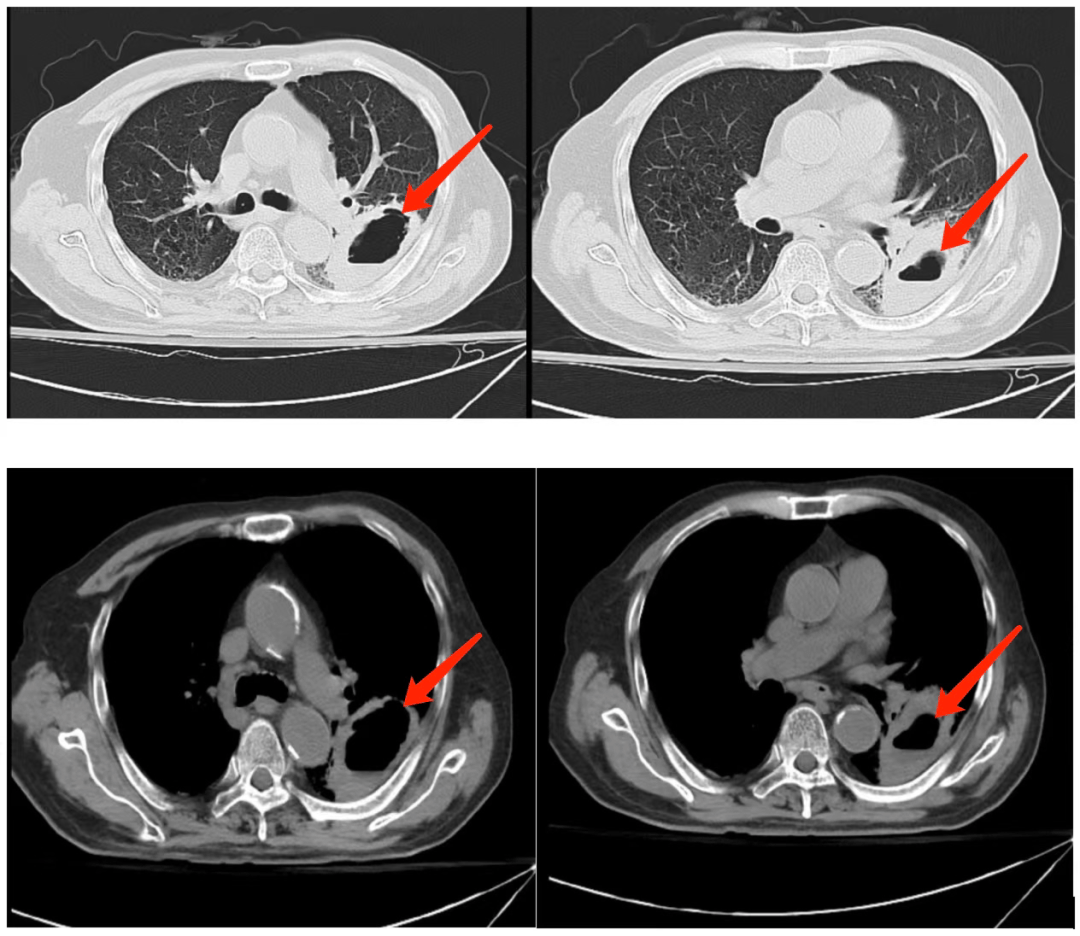

"患难兄弟"的脓胸治疗在肺科医院实现转机

绝非易事,纤维板剥脱手术难度较大,胸腔粘连严重,易造成大出血,肺破裂